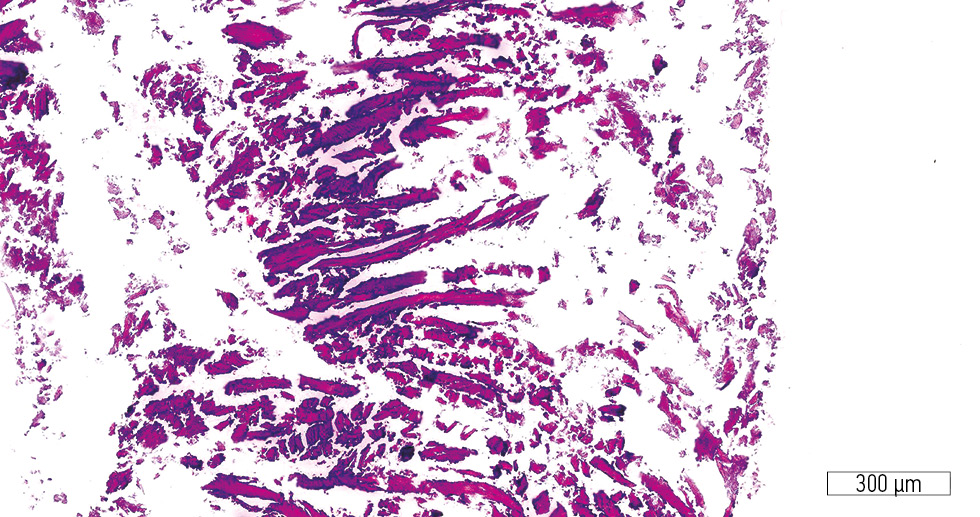

In the control group, numerous bone chip fragments were observed. Neither an obvious stromal component nor structured bone trabeculae were identified (Fig. 5). Isolated regions of active stromal component with pronounced vascularization were present. The bone trabeculae appeared immature, with osteoblasts and newly formed lacunae containing osteocytes (Fig. 6).

Fig. 5. Numerous bone fragments without stromal component or newly formed trabeculae (control group). Hematoxylin-eosin stain; original magnification ×200.